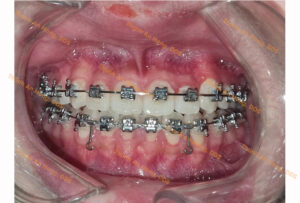

HÌNH ẢNH THỰC TẾ

Chỉnh mắc cài giảm hô